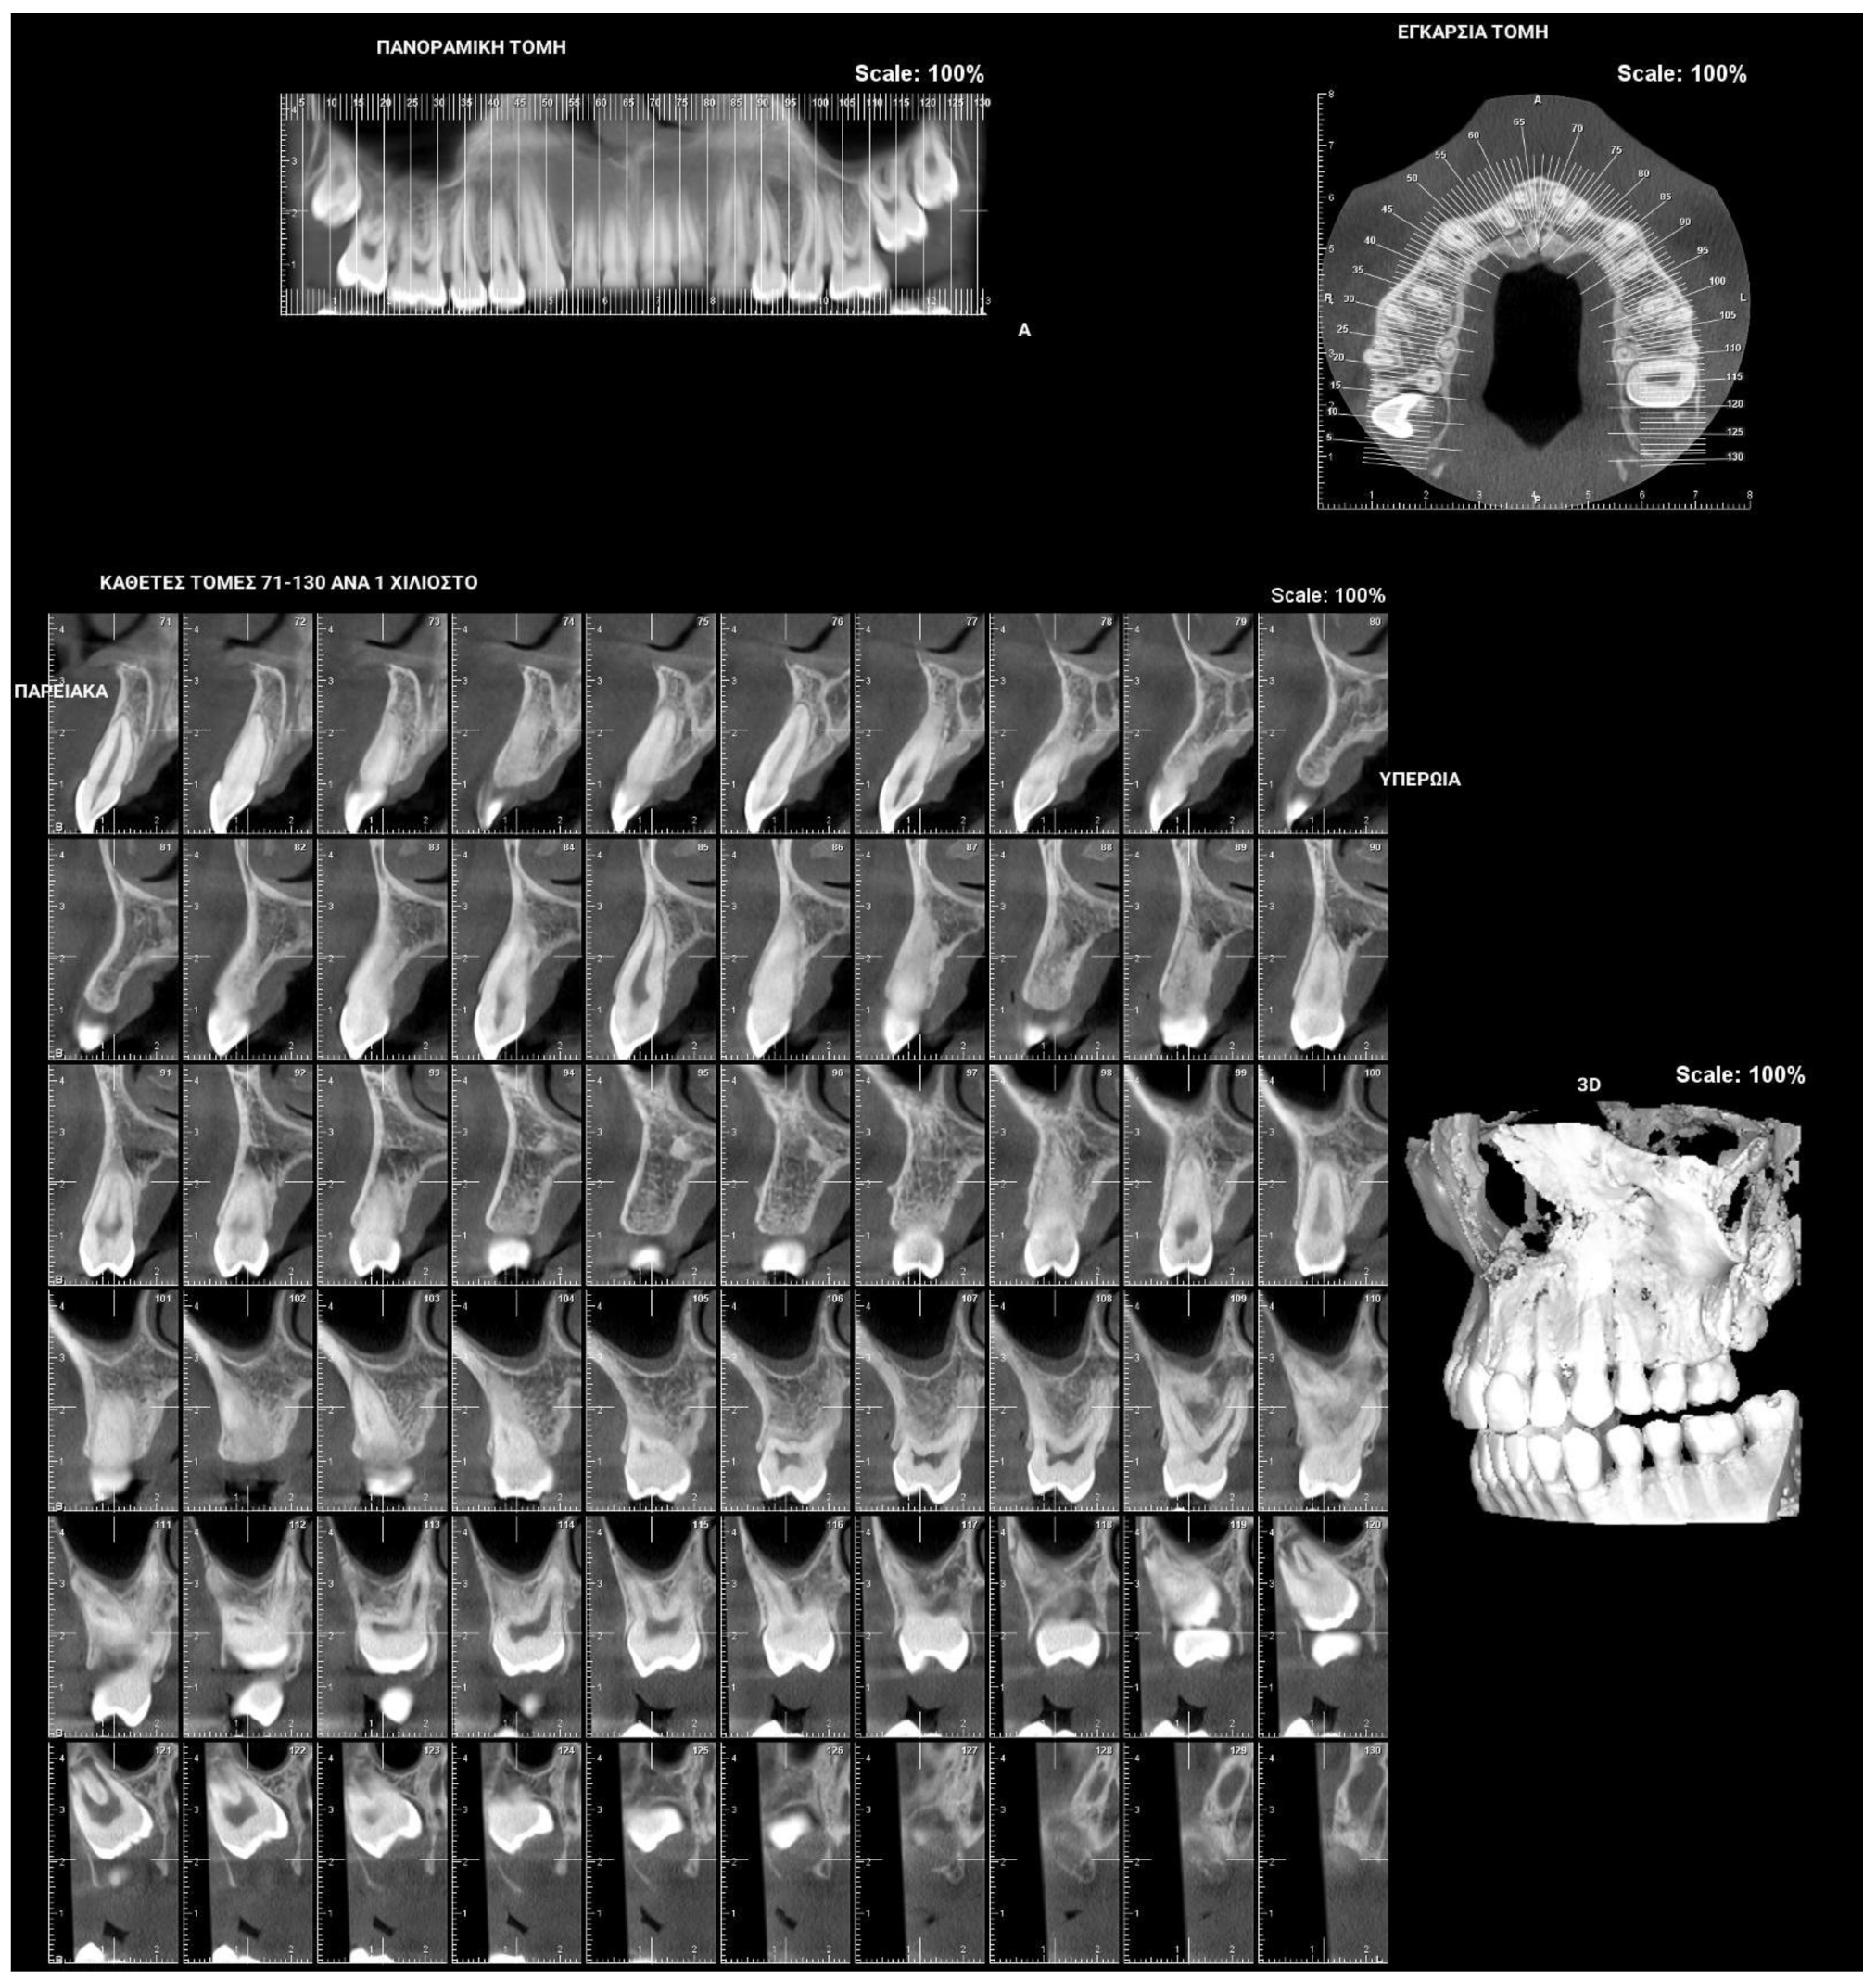

Figure 1.

Patient presenting eruption failure of the upper left second molar due to primary retention.

Figure 2.

The phenomenon where molars cease to erupt before they emerge, without a physical barrier in the eruption path or as a consequence of an atypical location, is defined as primary retention. The alveolar support of a primarily retained molar, which does not resorb occlusally, is considered a normal barrier to the eruption path. Primary retention is similar to “unerupted” and “embedded” teeth [9]. In the event that the eruption of a permanent tooth is at least 2 years delayed compared to what is normally expected, primary retention should be a clinical entity to take into account. A radiographical follow-up of a minimum of 6 months is suggested as an initial control to determine whether the tooth is showing any eruptive movement or not [10]. The suggested radiographic methods include a periapical or even panoramic X-ray. Primary retention is the possible result of a disturbance in the dental follicle that does not succeed in initiating the metabolic events responsible for bone resorption in the eruption traject [11] (Figure 1 and Figure 2).